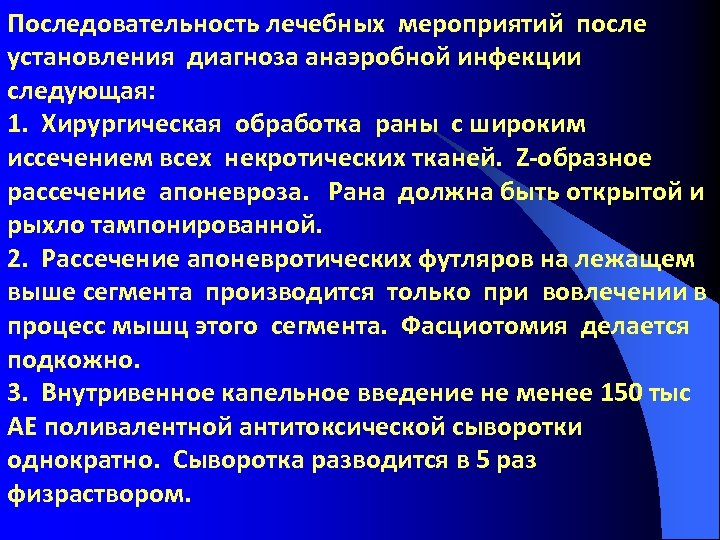

Последовательность лечебных мероприятий после установления диагноза анаэробной инфекции следующая: 1. Хирургическая обработка раны с широким иссечением всех некротических тканей. Z-образное рассечение апоневроза. Рана должна быть открытой и рыхло тампонированной. 2. Рассечение апоневротических футляров на лежащем выше сегмента производится только при вовлечении в процесс мышц этого сегмента. Фасциотомия делается подкожно. 3. Внутривенное капельное введение не менее 150 тыс АЕ поливалентной антитоксической сыворотки однократно. Сыворотка разводится в 5 раз физраствором.

Последовательность лечебных мероприятий после установления диагноза анаэробной инфекции следующая: 1. Хирургическая обработка раны с широким иссечением всех некротических тканей. Z-образное рассечение апоневроза. Рана должна быть открытой и рыхло тампонированной. 2. Рассечение апоневротических футляров на лежащем выше сегмента производится только при вовлечении в процесс мышц этого сегмента. Фасциотомия делается подкожно. 3. Внутривенное капельное введение не менее 150 тыс АЕ поливалентной антитоксической сыворотки однократно. Сыворотка разводится в 5 раз физраствором.

4. Инфильтрирование тканей в окружности раны антибиотиков. 5. Взятие материала из раны для бактериологического анализа. 6. При быстро распространяющемся процессе - ампутация как можно раньше. 7. Инфузионная терапия. 8. Форсированный диурез. 9. Дезинтоксикация. 10. Массивная антибиотикотерапия.

4. Инфильтрирование тканей в окружности раны антибиотиков. 5. Взятие материала из раны для бактериологического анализа. 6. При быстро распространяющемся процессе - ампутация как можно раньше. 7. Инфузионная терапия. 8. Форсированный диурез. 9. Дезинтоксикация. 10. Массивная антибиотикотерапия.